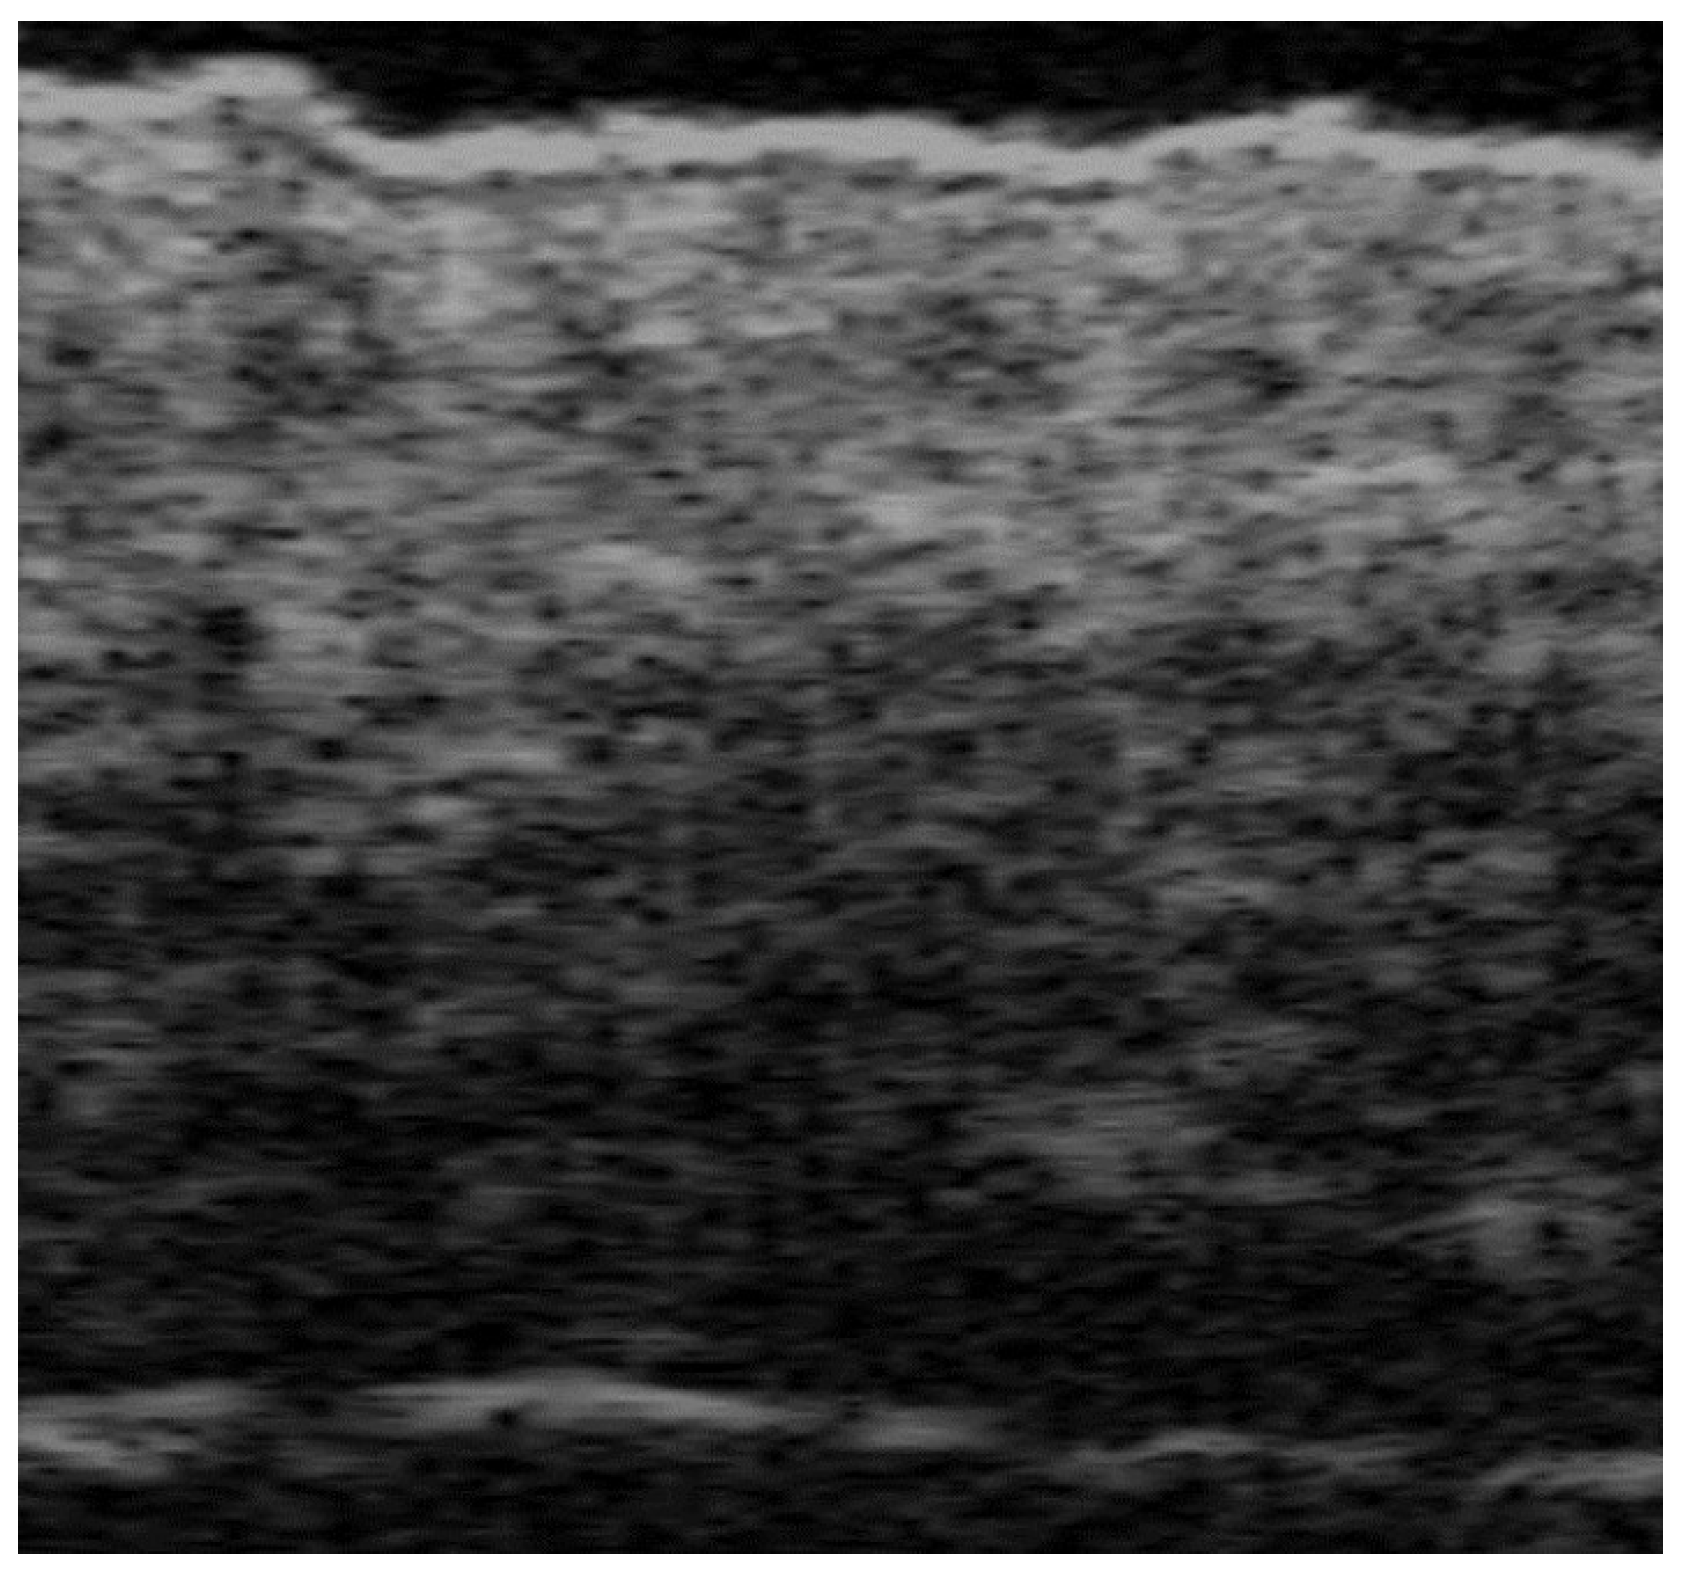

5. Specific Cutaneous Structure and Sites of Skin Disorders